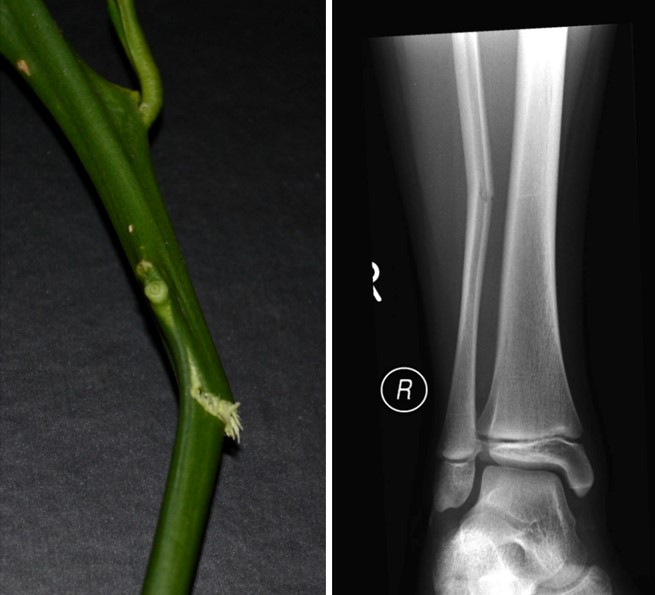

Greenstick Fracture

Common in children, where the bone bends and cracks but doesn't break completely, similar to a green twig.

Common in children Incomplete fracture Quick healing